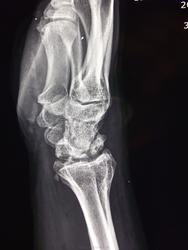

Пол пациента: Мужской пол Тип патологии: Воспалительное заболевание неинфекционной природы Область исследования: Скелетно-мышечная система Методы исследования: Rg Вот такая картина асептического некроза. https://radiomed.ru/sites/default/files/styles/case_slider_image/public/user/8914/dscf2062.jpg?itok=nVp3VX7z https://radiomed.ru/sites/default/files/styles/case_slider_image/public/user/8914/dscf2060.jpg?itok=MS7pXnEt ID:23778 Чт, 18/10/2012 - 19:13 #1 Роман Муравьев Не на сайте Был на сайте: 4 года 9 месяцев назад Зарегистрирован: 02.10.2010 - 20:09 Публикации: 191 Интересно, как давно начало беспокоить Чт, 18/10/2012 - 21:06 #2 maker4ik Не на сайте Был на сайте: 8 лет 6 месяцев назад Зарегистрирован: 19.10.2011 - 17:49 Публикации: 2682 Печалька... Пт, 19/10/2012 - 02:30 #3 Демчев Валентин... Не на сайте Был на сайте: 7 лет 7 месяцев назад Зарегистрирован: 08.02.2011 - 15:40 Публикации: 445 Боли ноющего характера в течении нескольких лет, функция не нарушена. В анамнезе неоднократно травмы. Пт, 19/10/2012 - 09:41 #4 Almo Не на сайте Был на сайте: 6 часов 30 минут назад Зарегистрирован: 28.09.2008 - 18:50 Публикации: 8247 Могу предположить , что профессия связана с металлобработкой. Пт, 19/10/2012 - 10:14 #5 Pticin86 Не на сайте Был на сайте: 6 лет 4 месяцев назад Зарегистрирован: 19.10.2011 - 14:46 Публикации: 9 Данные пациента стоило бы убрать. Пт, 19/10/2012 - 15:37 #6 Брысковский Дмитрий Не на сайте Был на сайте: 9 месяцев 1 неделя назад Зарегистрирован: 08.11.2011 - 11:00 Публикации: 187 Кинбека None are more hopelessly enslaved than those who falsely believe they are free Пт, 19/10/2012 - 18:02 #7 Демчев Валентин... Не на сайте Был на сайте: 7 лет 7 месяцев назад Зарегистрирован: 08.02.2011 - 15:40 Публикации: 445 Almo wrote: Могу предположить , что профессия связана с металлобработкой. Его работа не связана с физической нагрузкой, в анамнезе были неоднакратные травмы, обострение возникло после того как что-то ремонтировал в машине.

Боли ноющего характера в течении нескольких лет, функция не нарушена. В анамнезе неоднократно травмы.

Кинбека